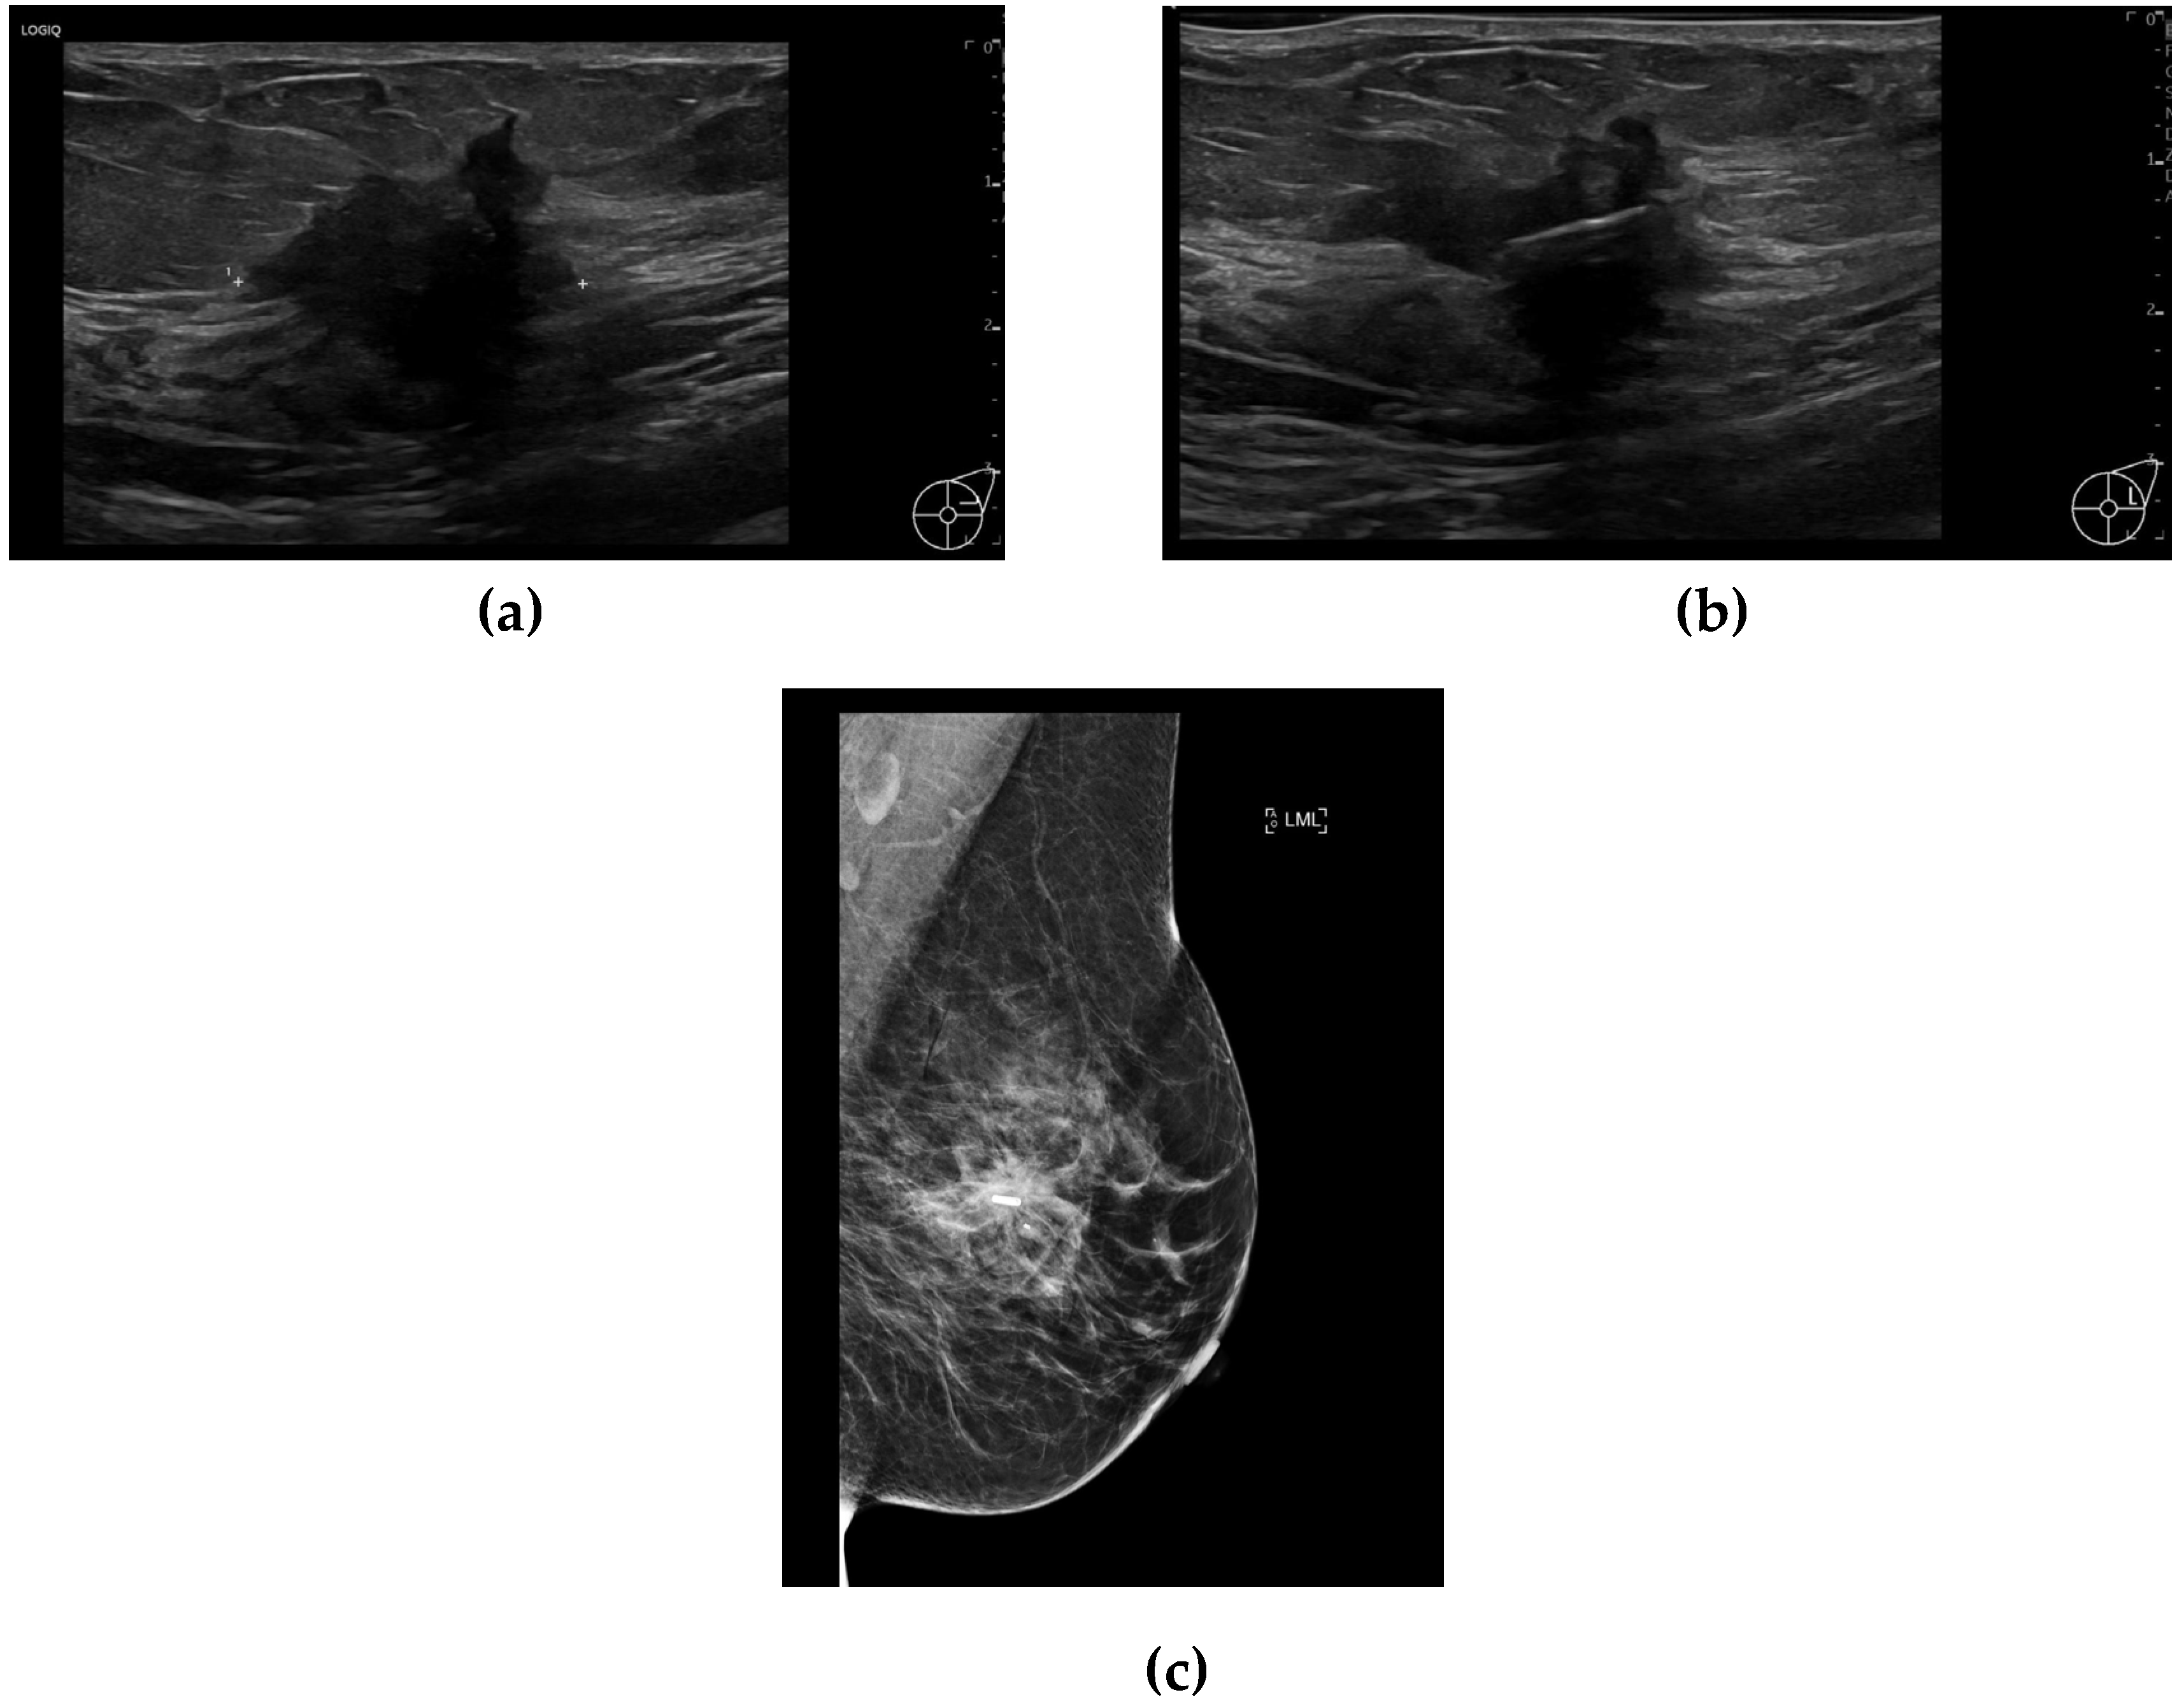

The RFID tags were inserted by either a consultant breast radiologist or a breast radiology trainee under ultrasound or mammographic guidance (Figure 1a, 1b, and 1c). Tag insertion was performed during a dedicated appointment prior to surgery, allowing for preoperative planning and minimizing logistical challenges on the day of surgery. The LOCalizer system comprises a unique RFID tag, which measures approximately 11 mm in length and 2 mm in diameter, deployed using a 12-gauge introducer. Each tag includes a polypropylene cap designed to prevent migration within the breast tissue, ensuring stability throughout the preoperative period. After tag insertion, a handheld portable reader displays the distance to the tag in millimeters, which is particularly valuable when deploying more than one tag (e.g., in cases of bracketing or multifocal disease). The system also assigns an individual ID tag number, which is recorded in the patient’s medical notes (Figure 2a and 2b), facilitating accurate intraoperative retrieval.

Figure 1. (a) Ultrasound of the left breast demonstrates a 25 mm hypoechoic, irregular lesion within the upper outer quadrant which was also noted to have internal vascularity. Biopsy results yielded invasive ductal carcinoma (grade 3). (b) Ultrasound image obtained during localisation shows a tag deployed within the centre of the lesion. (c) Mediolateral oblique view post-localisation mammogram of the left breast shows successful tag placement within the centre of the lesion.